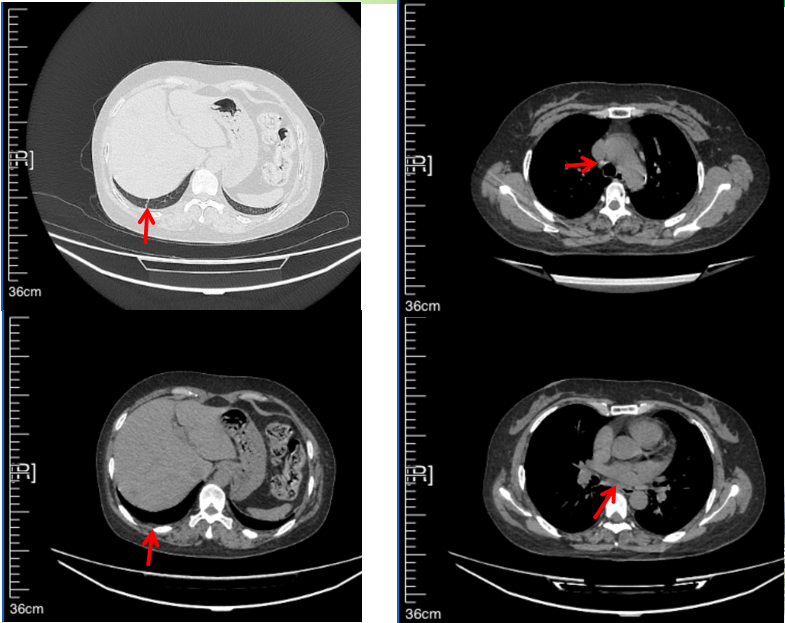

2016年1月复查CT提示支气管截断可见新发小结节,一线治疗采用培美曲塞+DDP方案化疗4周期(培美曲塞3.36,DDP 480mg)。化疗后复查胸部CT:右肺见不规则结节样影,最大层面大小约19mm*8mm,较前比较明显增大,疗效评估PD。2017.3-2017.4予单药多西他赛化疗3周期,疗效评估SD。2018年5月末复查CT提示结节较前增大,评效为PD,2018年6-10月予多西他赛+CBP化疗4周期,疗效评估SD。2022年5月患者出现活动后气短,复查胸部CT示右肺膨胀不良;右侧胸腔积液增多。胸腔积液包埋病理示符合肺腺癌细胞。行NGS基因检测:EML4:exon13-ALK:exon20融合。PD-L1(克隆号22C3)TPS<1%。

2018.07

2022.05